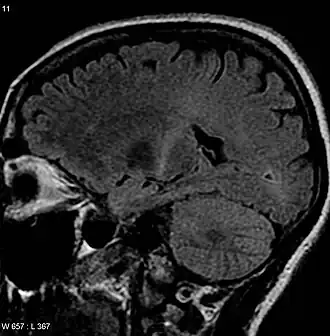

| Uma MRI com sinal aumentado na parte posterior da cápsula interna que pode rastrear o córtex motor que é consistente com o diagnóstico de ELA | |